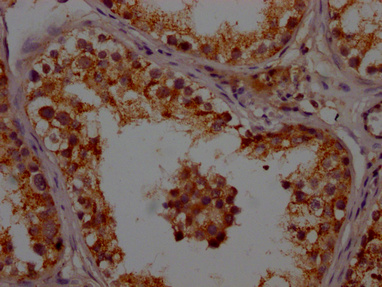

IHC image of PACO64147 diluted at 1:200 and staining in paraffin-embedded human testis tissue performed on a Leica BondTM system. After dewaxing and hydration, antigen retrieval was mediated by high pressure in a citrate buffer (pH 6.0). Section was blocked with 10% normal goat serum 30min at RT. Then primary antibody (1% BSA) was incubated at 4°C overnight. The primary is detected by a Goat anti-rabbit polymer IgG labeled by HRP and visualized using 0.05% DAB.